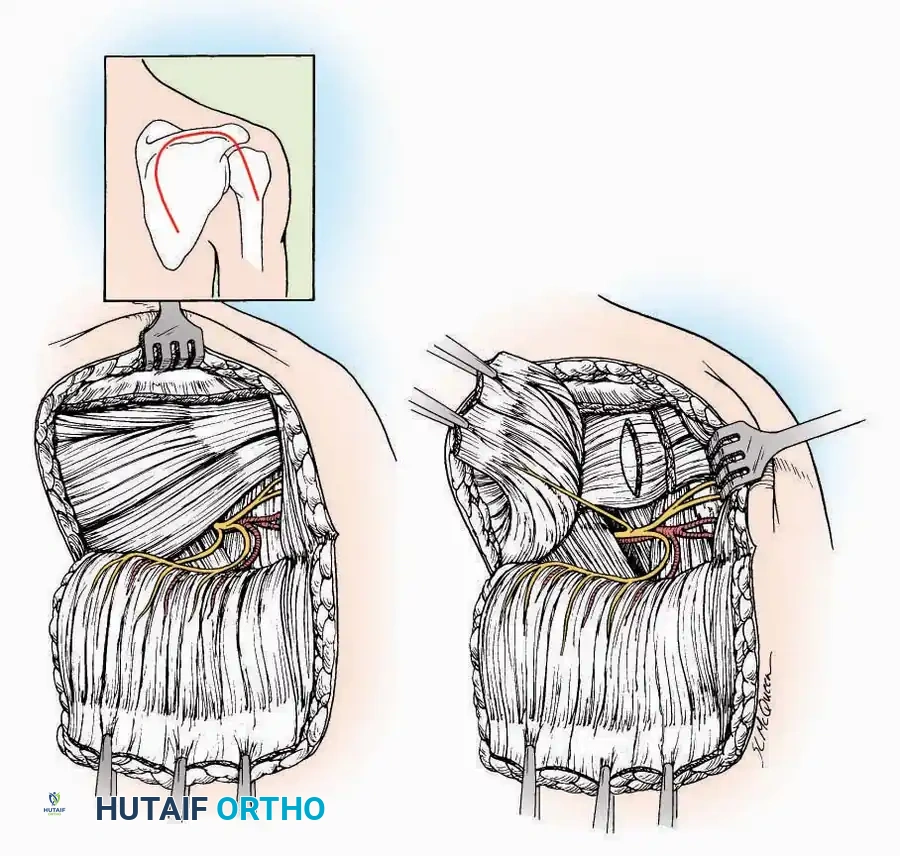

Surgical Technique:

* Incision: Begin just proximal to the IP joint and extend proximally for 5 cm, running parallel and strictly medial to the EHL tendon.

* Exposure: Divide the superficial fascia. Identify and retract the EHL tendon laterally.

* Capsulotomy: The capsule can be incised longitudinally in the exact plane of the skin incision, allowing for subperiosteal elevation of the capsule medially and laterally, preserving the vascular supply to the medial skin flap.